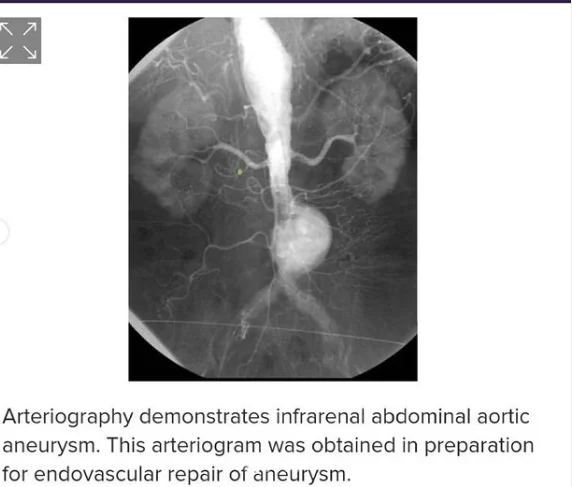

این بیماران با احساس ضربانات مداوم در شکم و درد و گاهاً بدون علامت در معرض خطر پارگی رگ اصلی بدن به نام آئورت ومرگ ناگهانی هستند .دیروز در کمتر از یکساعت بدون جراحی ، استنت هایی که پوشش دیواره ای دارند را مثل لوله داخل ناحیه آنوریسم/یا گشاد شده، تعبیه کردیم و آئورت به سایز نرمال برگشت.